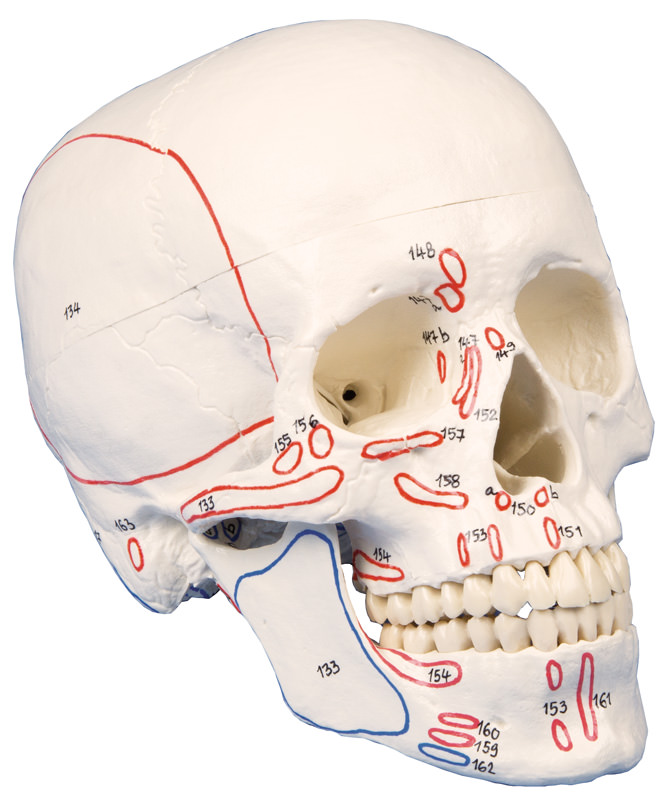

Schädelmodell wie Artikel 4500, jedoch zusätzlich mit Kennzeichnung der Muskelursprungs- und Ansatzfelder. Mit Nomenklatur.

MUSKELMARKIERUNG

Ideal für Physiotherapie-Schüler und Studenten! Auf der rechten Seite sind die Muskelursprünge (rot) und -ansätze (blau) markiert. Diese Kennzeichnung wurde in Zusammenarbeit mit Dozenten einer Physiotherapie-Schule entwickelt und orientiert sich speziell an den Anforderungen der Physiotherapie. Die Anleitung ist didaktisch nach der für Physiotherapeuten typischen Reihenfolge aufgebaut und verweist auch auf passende Literatur.